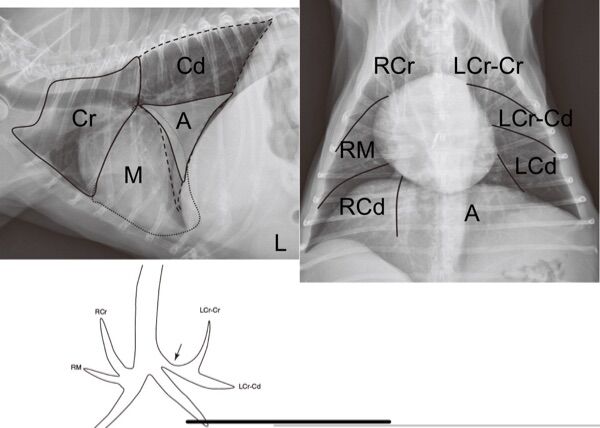

48.8歲公犬,出現喘及咳嗽,根據其X光影像,最不可能為下列何者?

(A)心因性肺水腫(cardiogenic pulmonary edema)

(B)吸入性肺炎(aspiration pneumonia)

(C)非心因性肺水腫(noncardiogenic pulmonary edema)

(D)出血(hemorrhage)